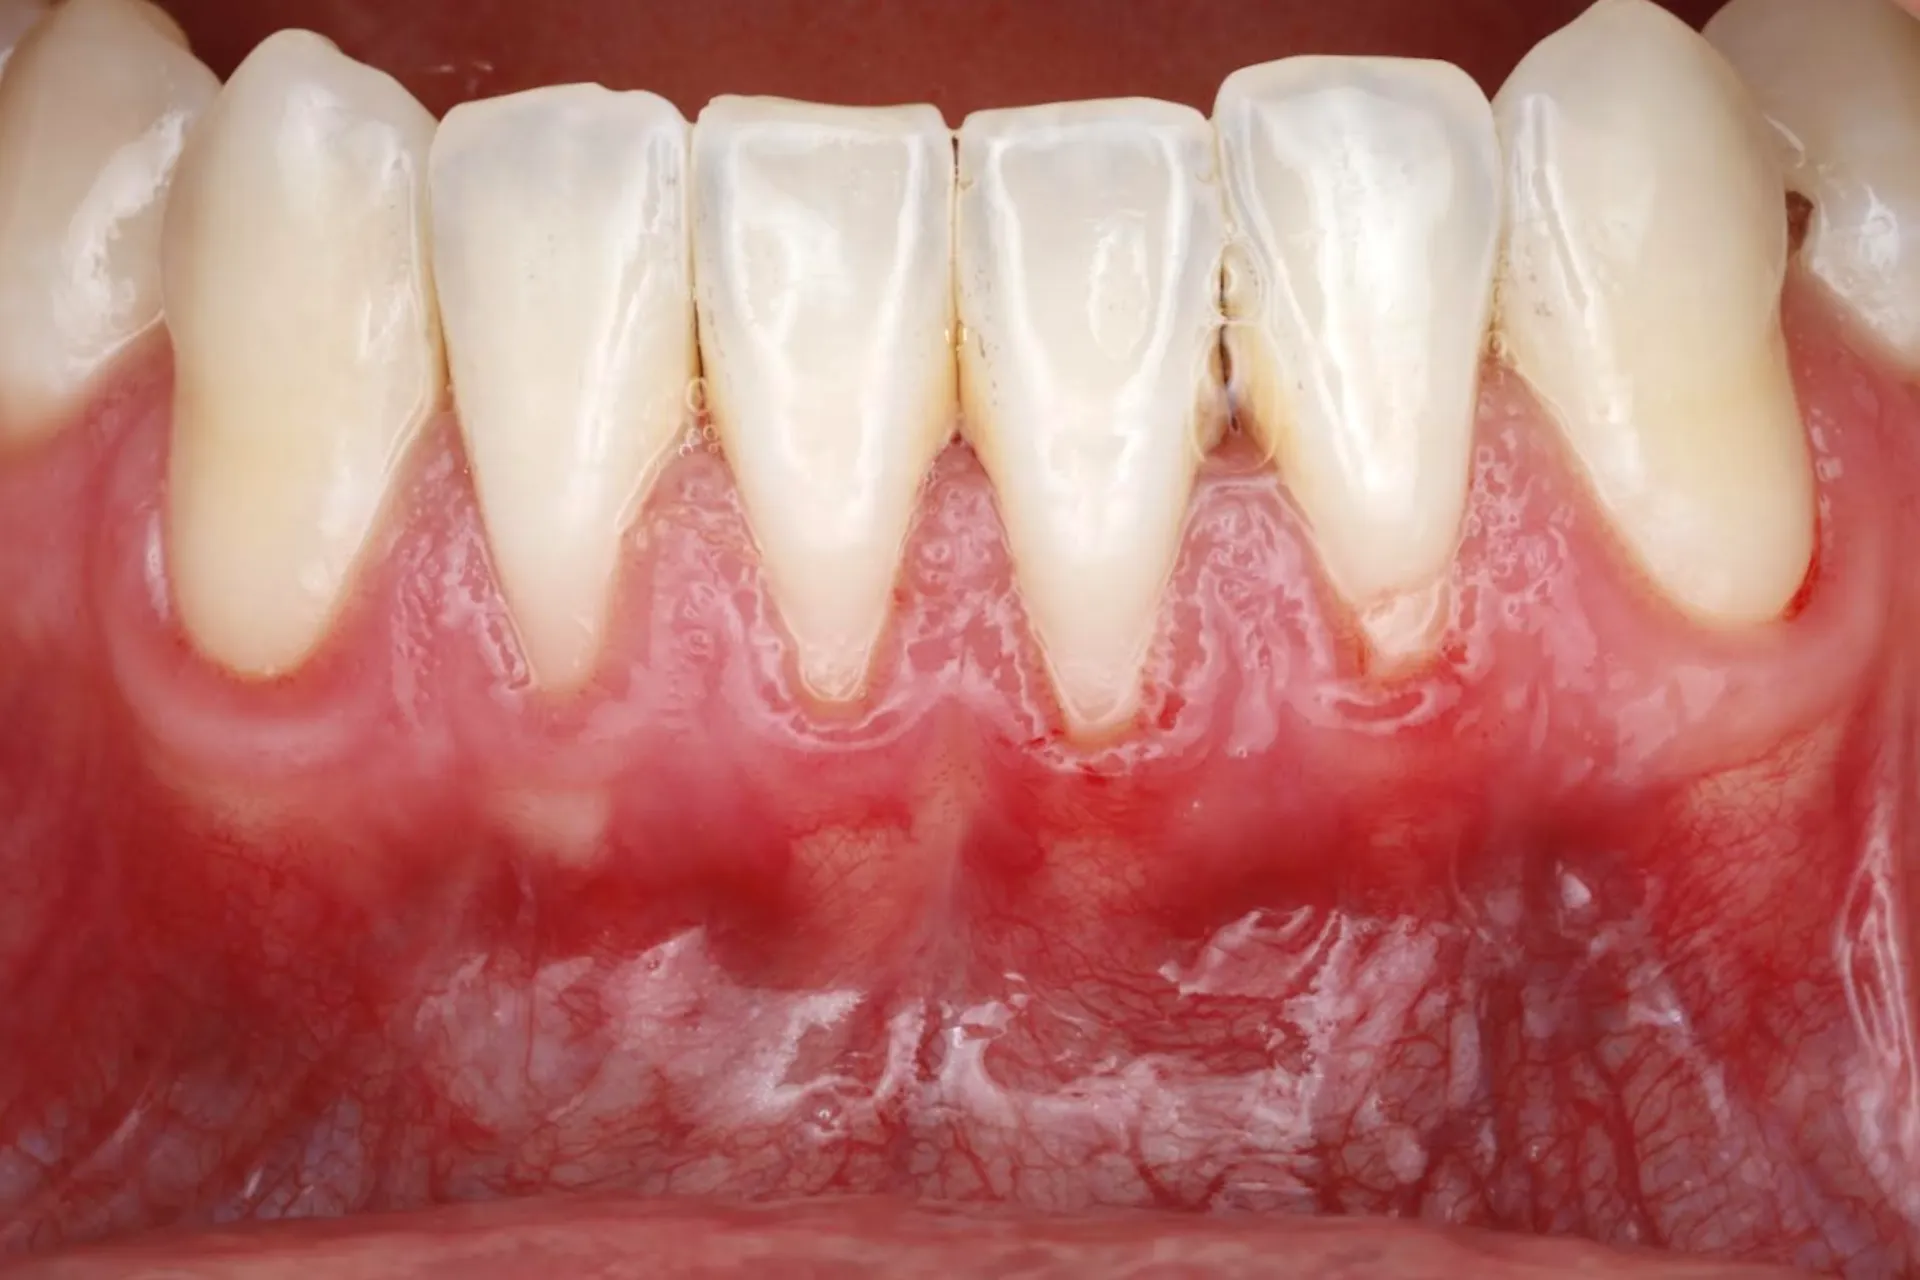

Gum Recession